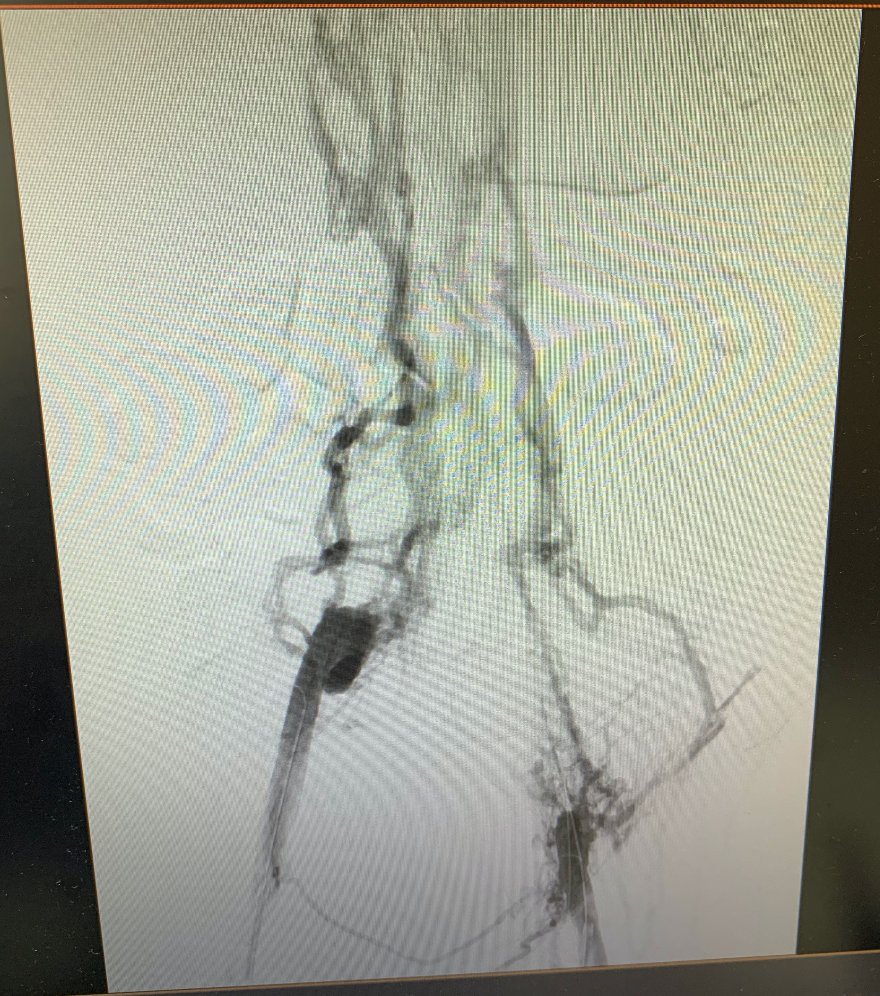

A great iliocaval reconstruction case for caval atresia. Check out the difference in the before and after! #medtwitter #veinmonday